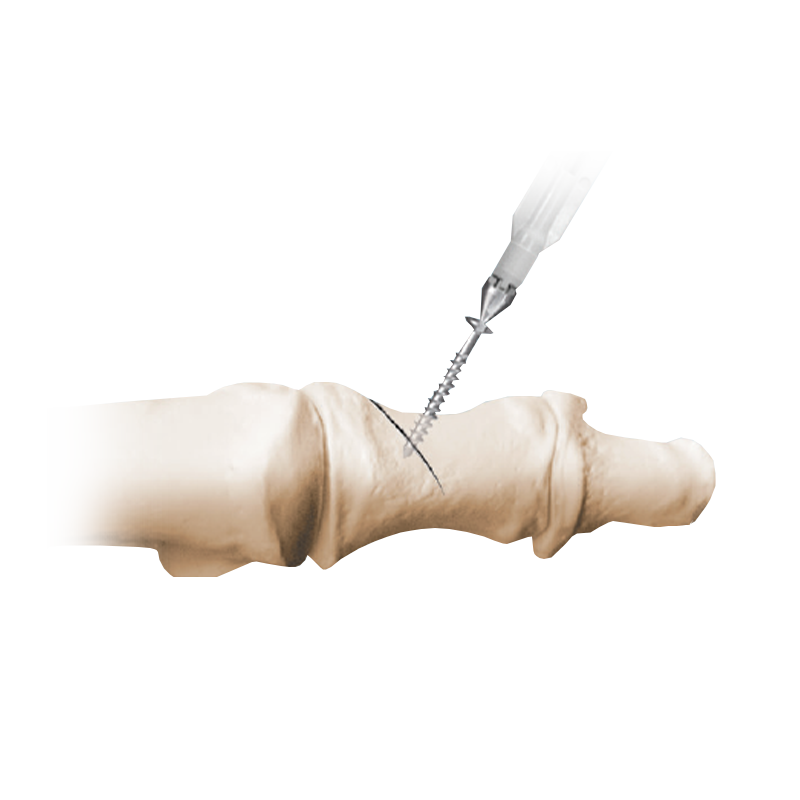

IBS™-B Beveled Screw System

IBS™-B Beveled Screw System delivers the strength, control, and versatility your MIS workflow demands.